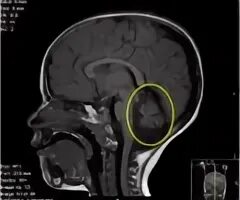

Денди уокера мрт